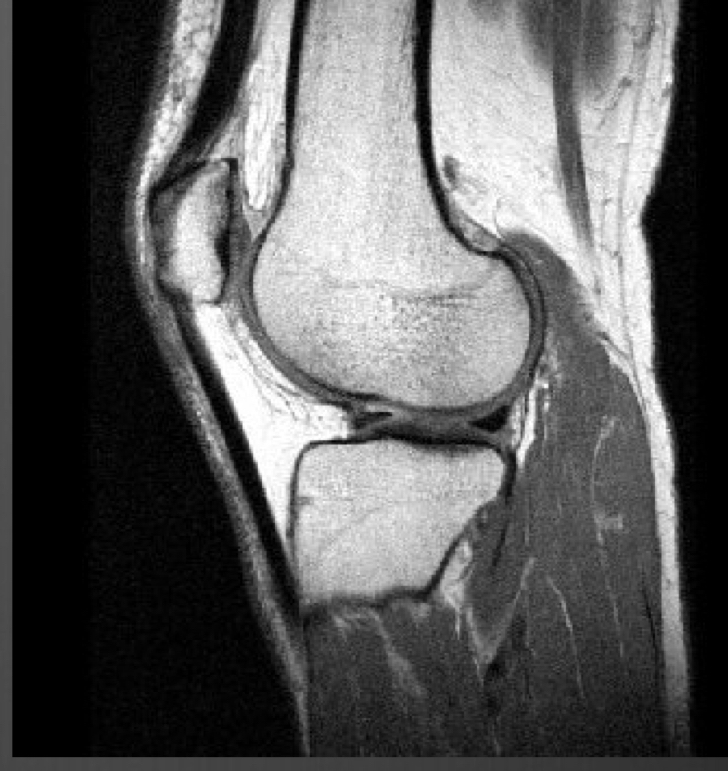

MRI indications

best for soft tissue

● Spinal cord injuries → MRI is imaging of choice*

● Occult fractures – hip (elderly), scaphoid ESP. if you can’t see on CT

● Tendons/Ligaments/Soft Tissue

○ MR Arthrography - contrast study of joints

○ Pre-op evaluation

● Certain complex fractures, infections

● Bone marrow abnormalities

● Avascular necrosis

T1 or T2

T1 because of black fluid